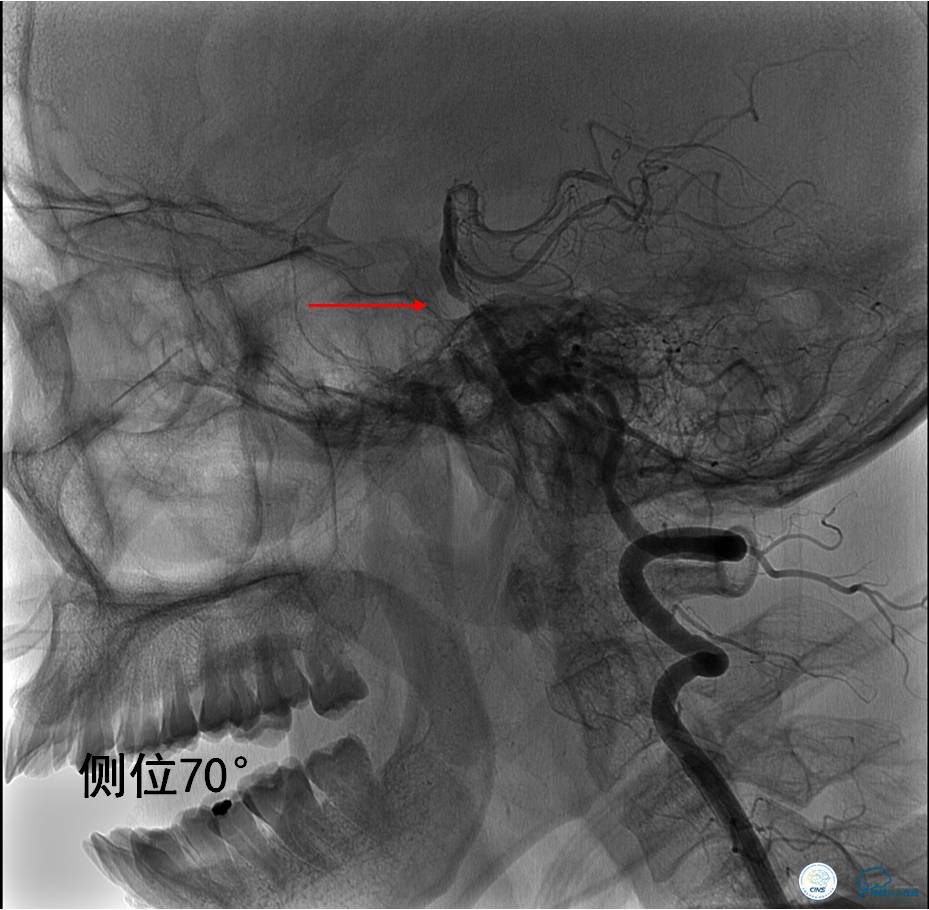

▼DSA显示基底动脉再次闭塞。

▼支架取栓(Solitaire 6×30)后:血流恢复,仍存在严重狭窄。

Q:支架取栓后仍存在严重狭窄该如何处理?

》根据中国卒中协会2015年指南:机械取栓后,再通血管存在显著的狭窄,建议密切观察,如TICI分级<2b级,建议行血管成形术(球囊扩张或支架置入)(IIb类推荐,B级证据)。

》该患者反复出现原位狭窄和闭塞,经讨论后决定行球囊扩张术+支架置入术。